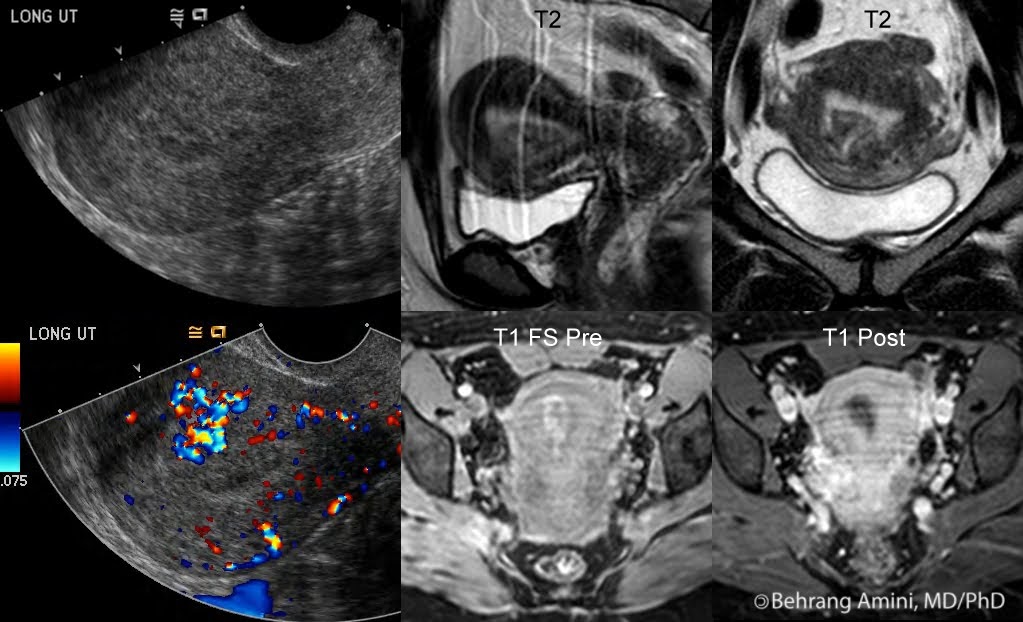

Retained Products Of Conception On Mri . The pathologic diagnosis of rpoc is made based on the presence of chorionic villi, which indicates persistent placental or trophoblastic tissue. Retained products of conception (rpoc) are a common and treatable complication after delivery or termination of pregnancy. Retained products of conception (rpoc) are a common and treatable complication after delivery or termination of pregnancy.